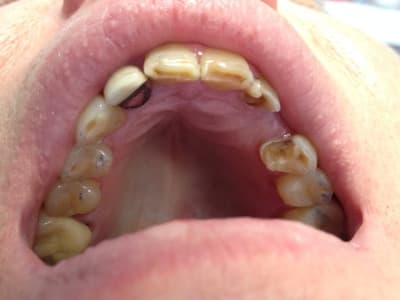

Ce monsieur que j'ai vu pour la première fois la semaine dernière vient pour remplacer la 23, il a eu précédemment un bridge collé qui lui a donné satisfaction pendant 15 ans. Il est tombé une fois il y a quelques années.

il aimerait améliorer l'esthétique des dents antérieures.

il ne se rend pas compte de son bruxisme et pense que les usures de ses dents sont liées au bridge collé.

c'est étonnant que le bridge collé ne se soit pas plus décollé ces dernières années, avec ce bruxisme.

Et que la 12 n'ai pas souffert d'avantage aussi (niveau paro).

Donc effectivement, il s'agit peut-être plus d'une erosion?